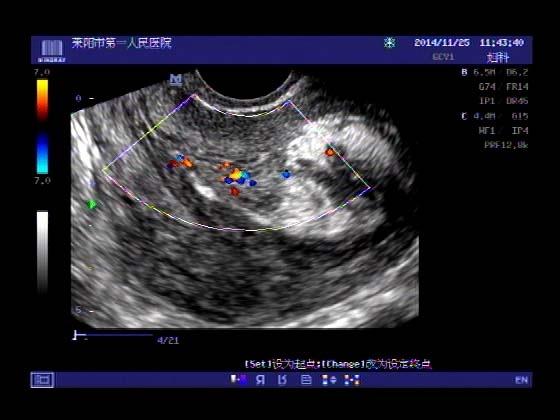

超声入门贴379---------粘膜下肌瘤(阴超的魅力)

女,43岁,月经量多3个多月,加重一个月

外院彩超检查提示:子宫后肌壁略高回声团------肌瘤?息肉?,盆腔少量积液

今天来我院检查:

巧妇难为无米之炊,经腹部超声确实很难定,阴超一目了然,乡镇医院诊断水平的提高更迫切的需要高档仪器的引进!